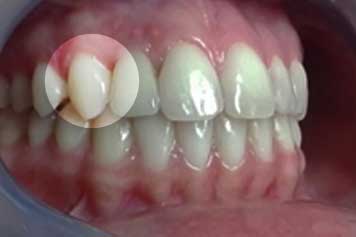

Etapa 2

Planificación quirúrgica del caso, y colocación de implante que repone incisivo lateral.

Implante por Agenesia Dentaria Implante por Agenesia Dentaria